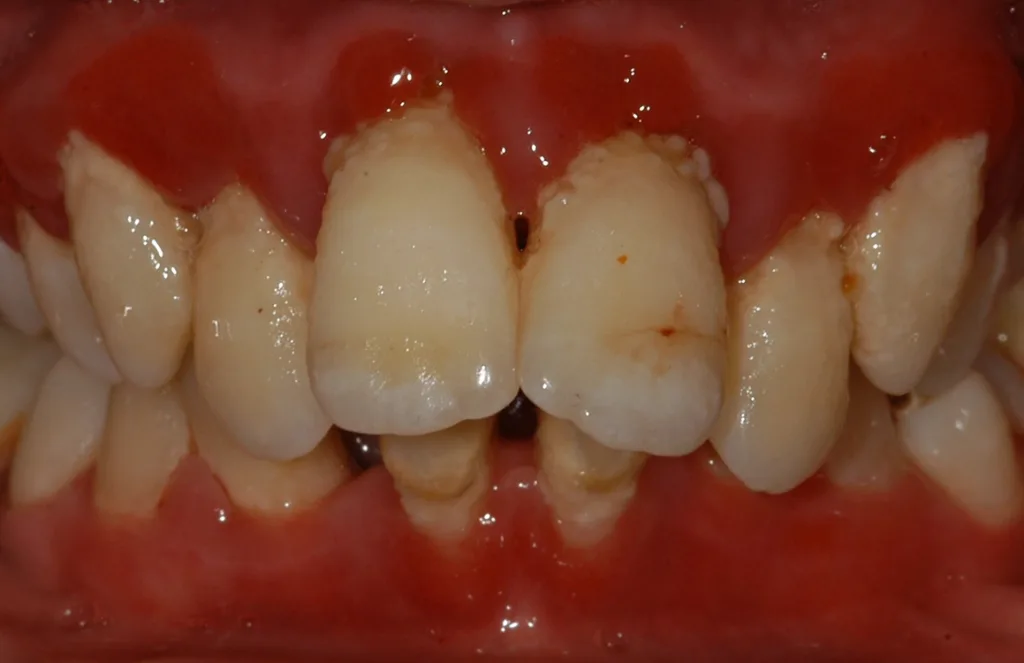

Die Ehlers-Danlos-Syndrome sind eine heterogene Gruppe von 13 unterschiedlichen Bindegewebserkrankungen, die alle durch Gelenkshypermobilitäten und überdehnbare und fragile Haut charakterisiert sind und je nach Typ mit unterschiedlichen weiteren Symptomen assoziiert sind [9]. Das parodontale Ehlers-Danlos-Syndrom (pEDS) ist das einzige der Ehlers-Danlos-Syndrome, das sich mit einer schweren Parodontitis im jugendlichen Alter, teilweise auch schon im Milchgebiss, manifestiert, da die Mutationen primär Gene der unspezifischen Immunantwort betreffen und erst in weiterer Folge die Bindegewebsschwäche verursachen [8] (Abb. 5, Abb. 6).

Die klinische Diagnose basiert auf der Trias der rasch progredienten Parodontitis im Teenageralter, dem kompletten Fehlen der befestigten Gingiva und der auffallenden Neigung zur Bildung von Hämatomen, die in zirka 80% der Betroffenen zu persistierenden Hämosiderin-Einlagerungen an den Schienbeinen führt. Die Parodontitis manifestiert sich teilweise schon im Milchgebiss, teilweise erst während der Pubertät und führt unbehandelt in wenigen Jahren zur Zahnlosigkeit. Das pEDS wird autosomal-dominant vererbt, sodass mindestens ein Elternteil ebenso an pEDS erkrankt ist; sehr selten kann es sich um eine Neumutation handeln. Die genetische Diagnose stützt sich auf die klinische Verdachtsdiagnose und wird durch den Nachweis pathogener Mutationen in den Komplement-1-Genen des C1S oder C1R gesichert.